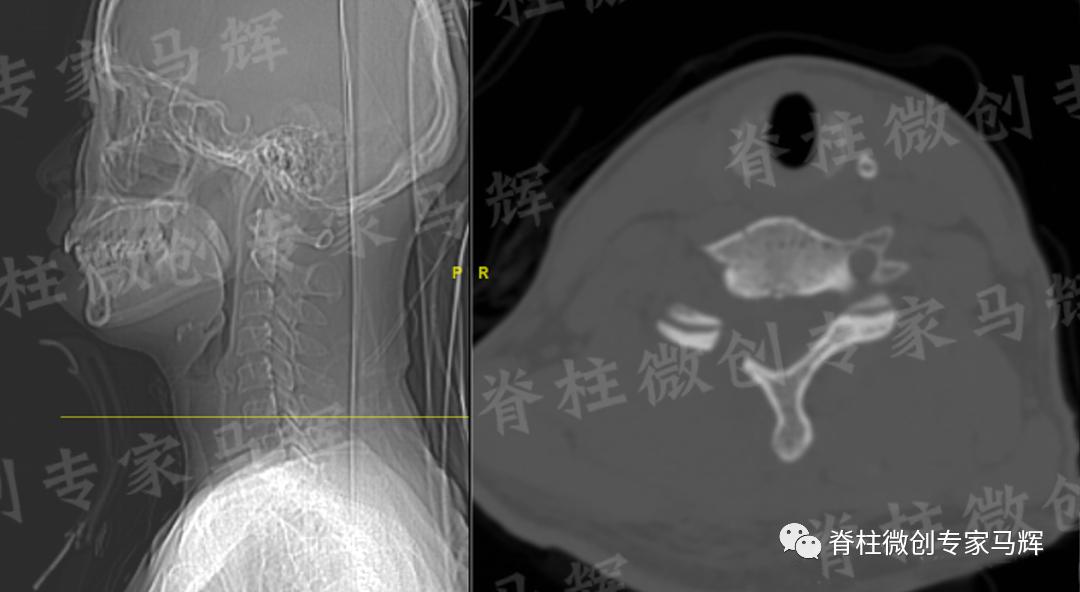

马主任仔细给患者做了检查,发现疼痛范围累及颈背部,及右上臂、前臂至手掌桡侧三指,无胸背部束带感,无行走不稳。根据影像学结果,诊断缪女士患6/7椎间盘突出症,属于神经根型颈椎病。

(术前)